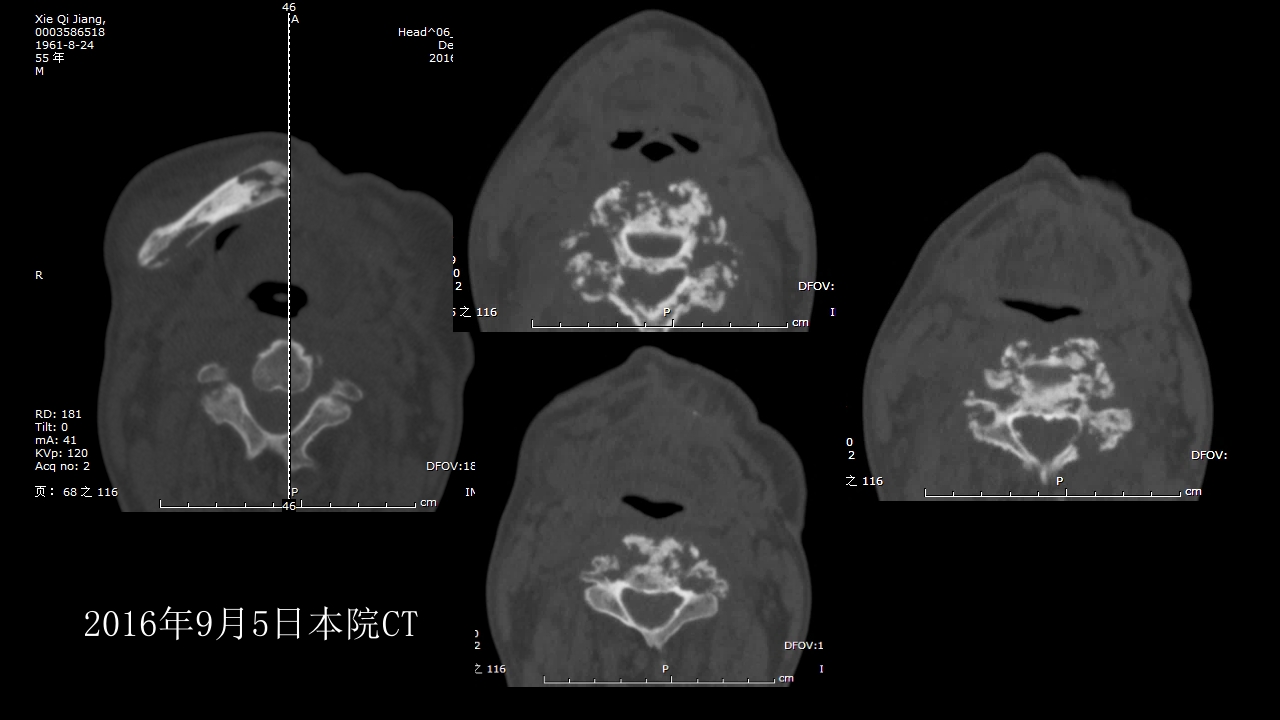

没有见过的弥漫性的骨质破坏